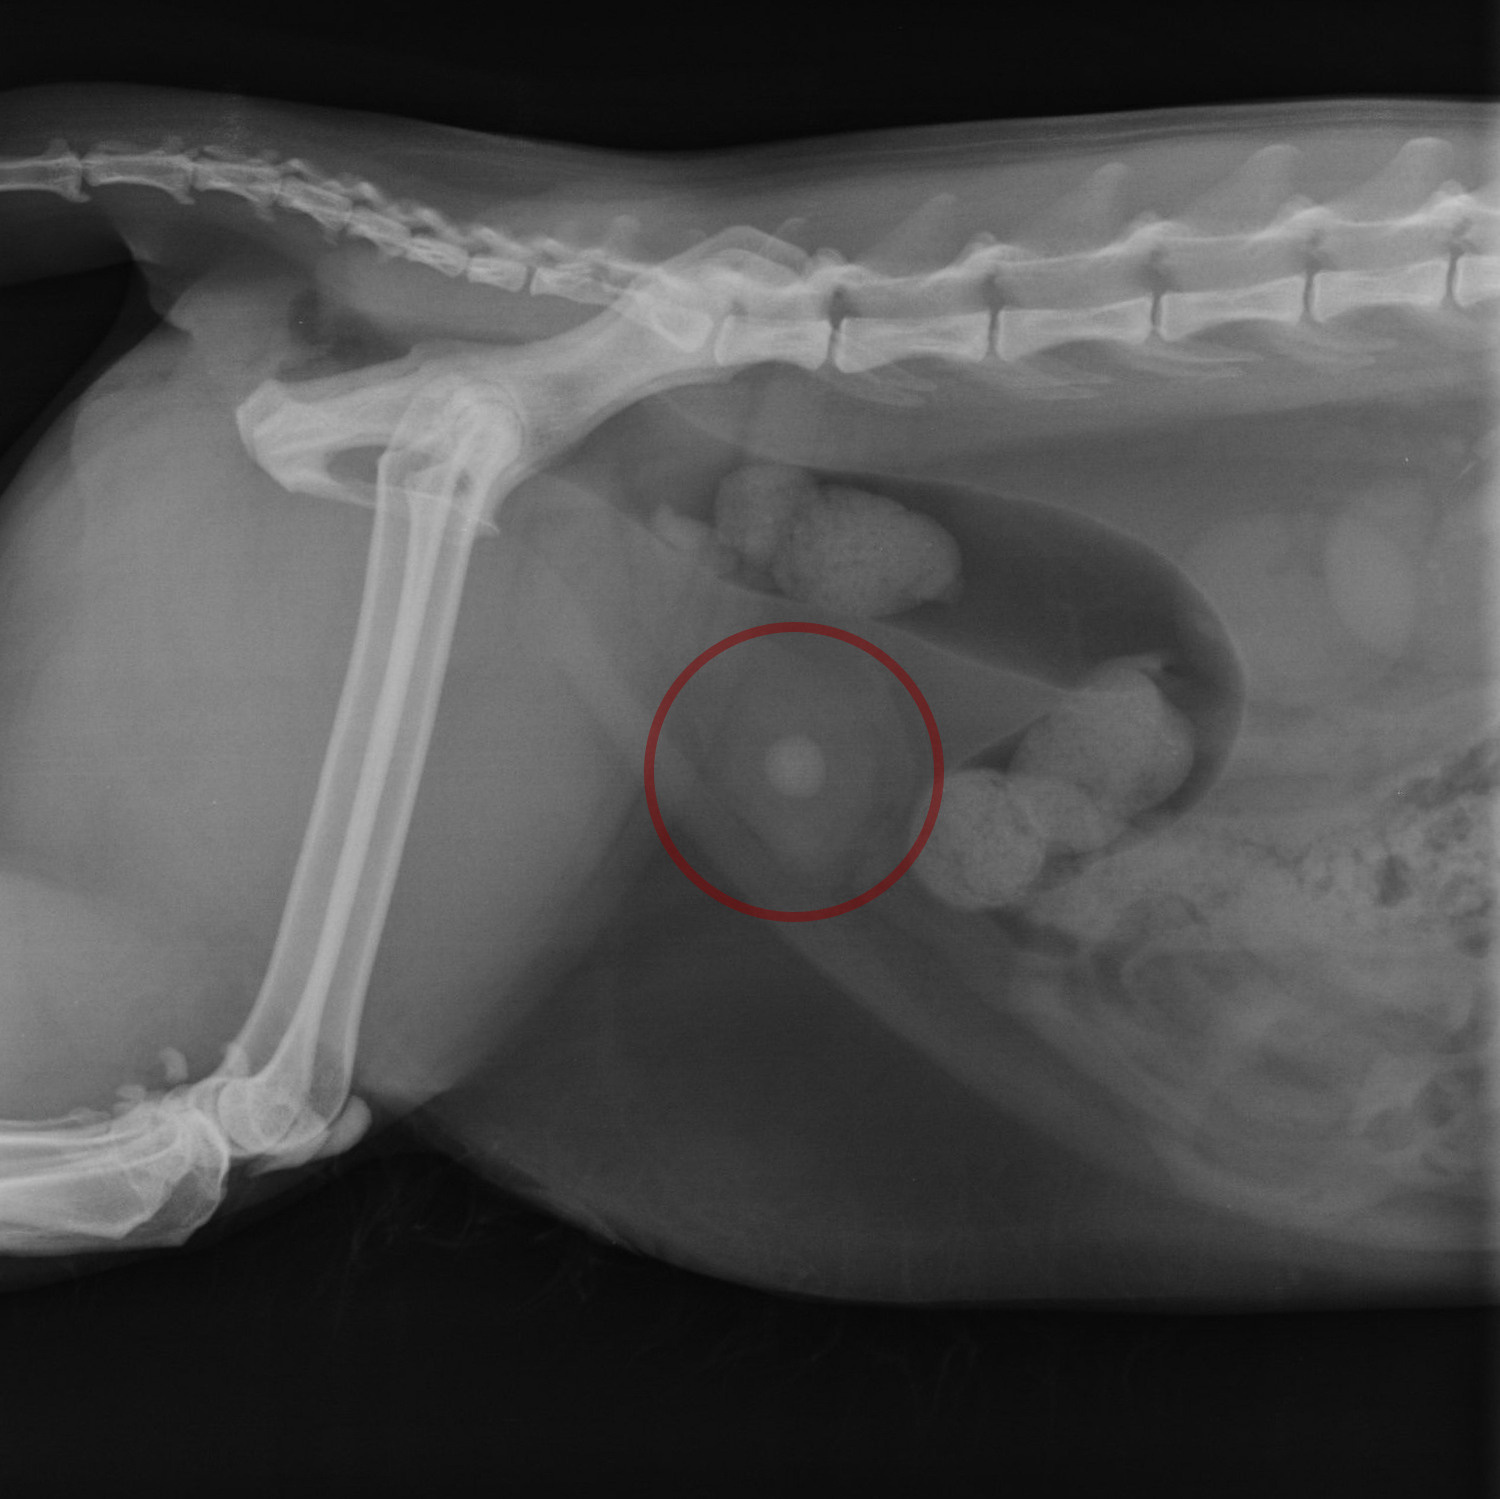

Визуализация камня с помощью рентген-диагностики